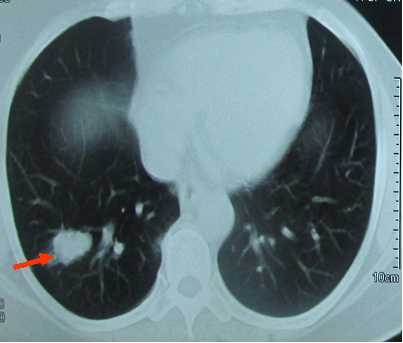

• CT scanner phổi, nốt di căn phổi phải kích thước (1,8x2)cm (hình 1).

Hình 1: Hình chụp CT lồng ngực cho thấy u phổi phải dạng di căn, kích thước (1,8x2)cm ngấm thuốc mạnh sau tiêm